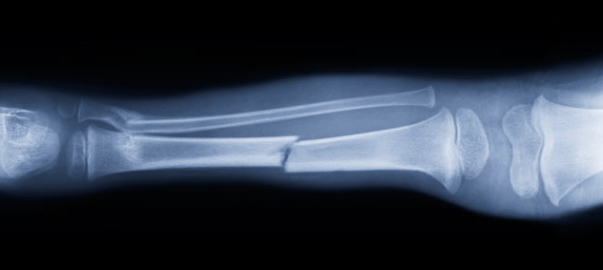

Nova har numera ett paket gips på sin arm, lindat i röd fin bandage. Allt började med att hon lekte i lekparken, men när hon hade klättrat upp och ställt sig på en parkbänk så tappade hon balansen och föll ner. Det gjorde självklart ont och hon blev ledsen, jag kollade så att hon kunde röra armen och om hon hade känseln kvar. Det verkade inte så farligt till en början, men efter att några klasskamrater råkade springa in i hennes onda hand några dagar senare så fick hon ännu ondare, så då åkte vi in till sjukhuset för att kolla upp så inget var brutet. Efter många timmars väntan så fick Nova tillslut röntga handleden där hon hade mest ont, och där kunde man se en början på en liten spricka i ett av benen.

Sprickan kommer att läka fint av sig själv, men för att skydda handleden lite extra så fick hon en liten gipsskena som skulle se till att handen inte böjer sig i onaturligt mycket och förvärrar sprickan. Nova tyckte det var superskoj, även om hon bara ska ha gipset någon vecka eller så. Efter en vecka ska vi tillbaka och röntga handleden igen och se om de kan ta bort gipset, men Nova tycker ju det är så coolt med gipsad arm så vi får se vad läkaren säger då. Hon behöver egentligen inte ha det så det var ingen fara inför skolavslutningen som väntar, tills dess skulle de definitivt ta bort det berättade läkaren vi träffade. To be continued…